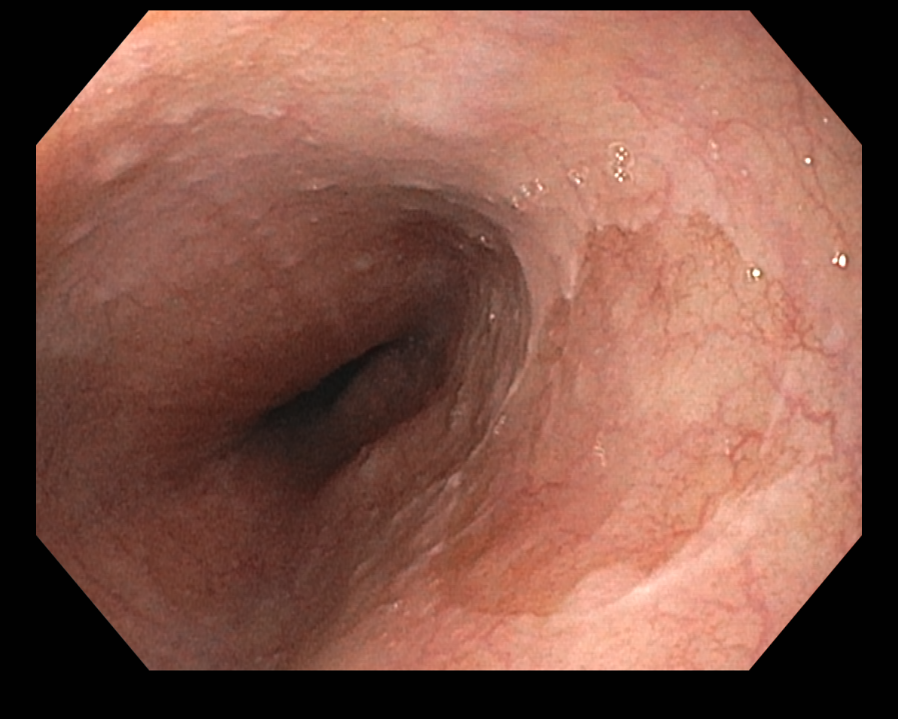

식도 상부에서 전형적으로 발견되는 위점막과 닮은 구별되는 영역. 일반 인구에서 유병률은 autopsy에서 약 5%인 반면 위내시경 연구에서는 상부위장관내시경을 시행하는 환자에서 0.4~11%. 내시경 연구에서 유병률이 더 낮은 이유는 inlet patches가 식도 상부에 위치하고 있기 때문인 것 같습니다. 가장 일반적으로는 UES 아래 식도 3 cm 부위에서 발견되며 이 부위는 일반적인 상부위장관내시경 동안에 잘 보여지는 곳은 아닙니다. Inlet patches는 모든 연령에서 기술되었지만 가장 일반적으로 발견되는 나이는 50대 중반입니다.